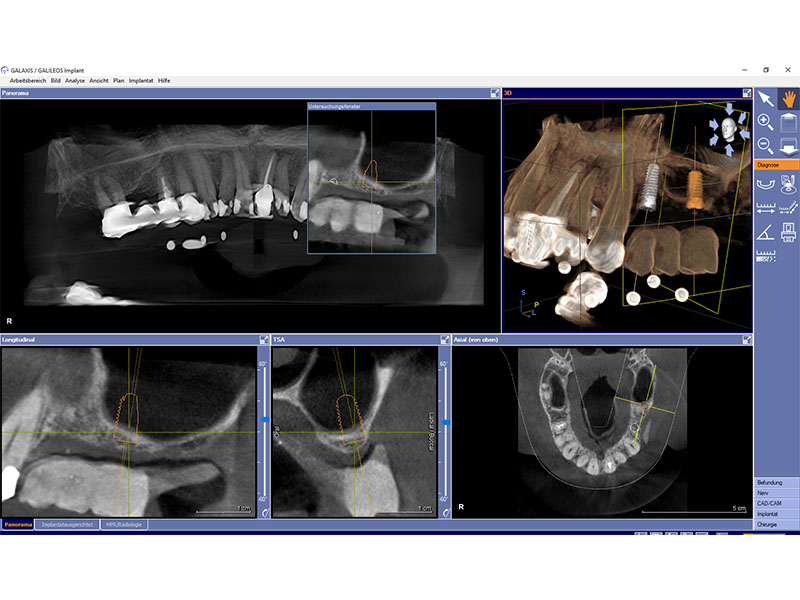

Zahnimplantate werden anhand von moderner virtueller 3D-Planung passgenau geplant und inseriert. Der Vorteil von Implantaten besteht darin, dass festsitzender ästhetischer Zahnersatz auch in solchen Fällen realisiert werden kann, in denen sonst nur herausnehmbare Prothesen möglich wären. Zudem ist im Gegensatz zur Brückenprothetik kein Beschleifen der Nachbarzähne notwendig.

Unter dentalen Implantaten versteht man im allgemeinen eine Schraube, die dort, wo ein oder mehrere Zähne verloren gegangen sind, in den Kieferknochen "eingepflanzt" wird. Diese Therapieform der Implantologie hat sich in den letzten Jahren zu einem alltäglichen Therapieverfahren in der Zahnheilkunde entwickelt. Wissenschaftliche Untersuchungen zeigen hierfür eine Erfolgsquote von i. d. R. 80-98 % über 10 Jahre. Verglichen mit anderen zahnärztlichen Maßnahmen gibt es nahezu keine andere Therapie mit derart guten Erfolgsaussichten. Auch eine Verbesserung der Lebensqualität wird durch implantatgetragenen Zahnersatz laut klinischer Studien erreicht.